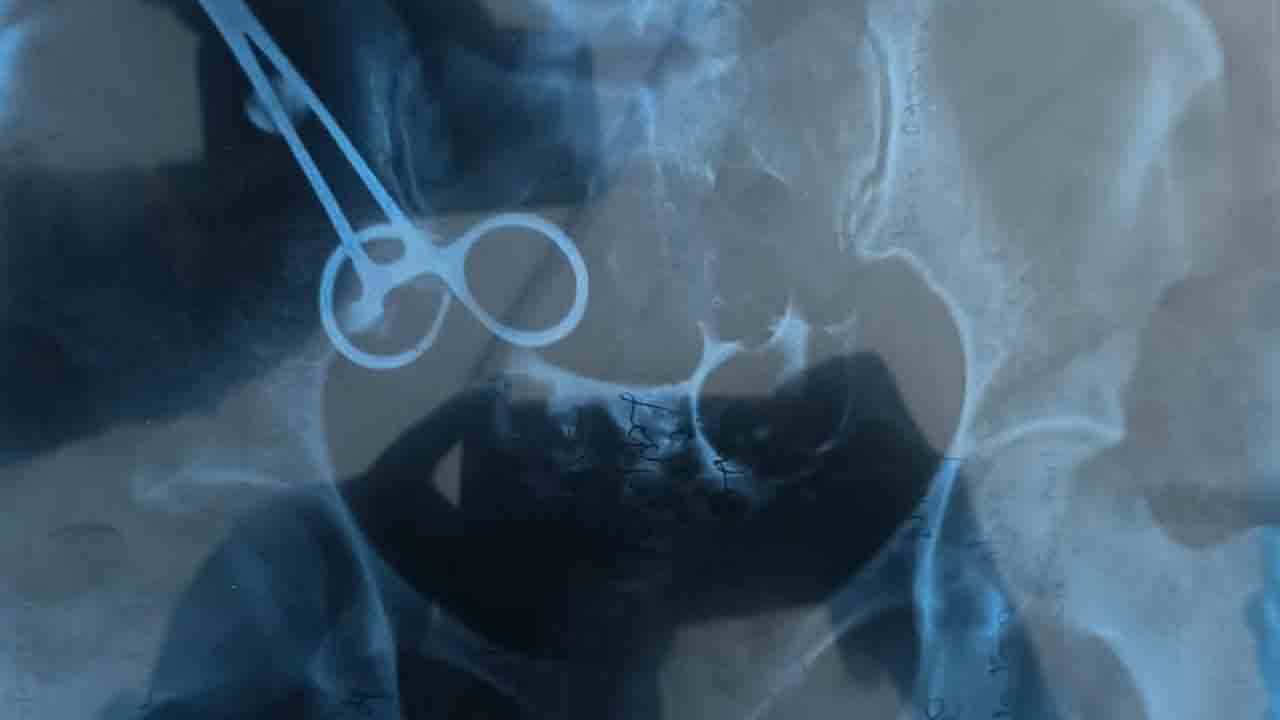

Doctor | ఆరేండ్ల కింద వైద్యురాలు ఓ మహిళకు డెలివరీ చేసి, కడుపులోనే కత్తెర మరిచిపోయి కుట్లు వేసిన ఘటన పెద్దపల్లి జిల్లా గోదావరిఖనిలో ఆలస్యంగా వెలుగులోకి వచ్చింది.